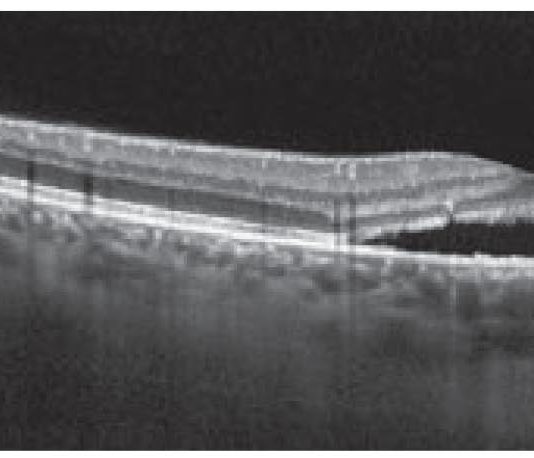

Desametasone a lento rilascio per risolvere l’edema maculare cistoide nella malattia...

INTRODUZIONE

Negli ultimi anni, l’utilizzo degli steroidi intravitreali a lento rilascio ha permesso di ottenere ottimi risultati anatomici...